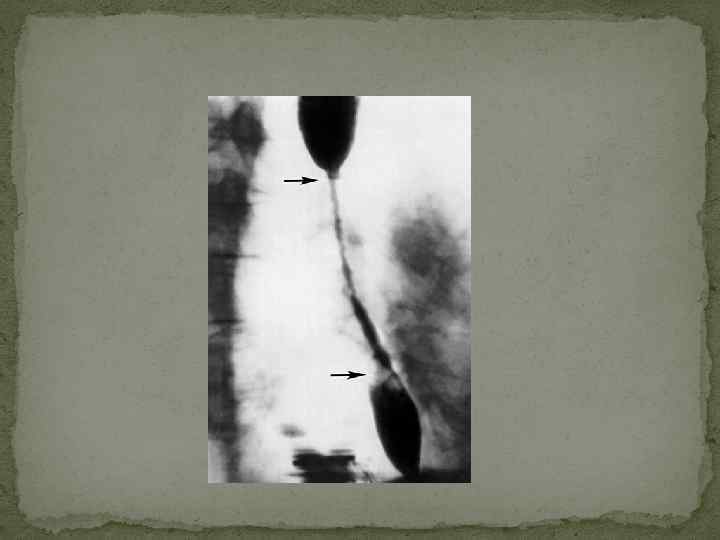

Грыжа пищеводного отверстия диафрагмы и обзор пищевода